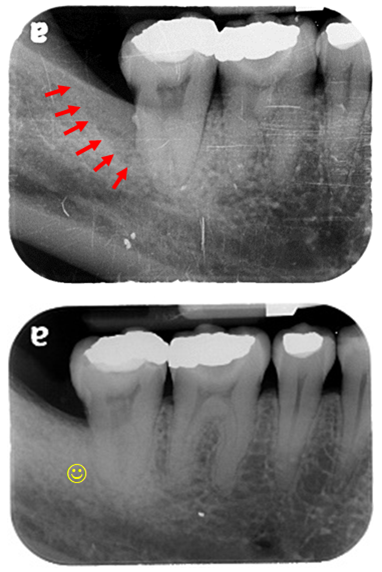

左側

右側

患者常抱怨早期拔完智齒後前一顆牙齒的牙肉反覆腫脹,經檢查發現......

發現左右邊的第二大臼齒 骨頭缺損嚴重

將骨頭缺失的地方,放骨粉及牙釉基質蛋白再生材料,將其縫合.........後續追蹤